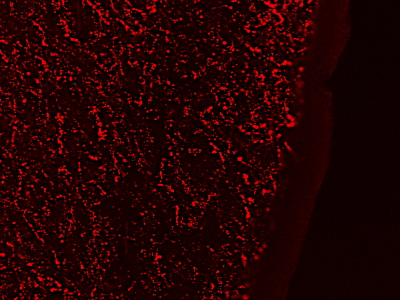

Product information "Anti-GAL, Internal"

Protein function: Contracts smooth muscle of the gastrointestinal and genitourinary tract, regulates growth hormone release, modulates insulin release, and may be involved in the control of adrenal secretion. [The UniProt Consortium]

| Application: | ELISA, ICC, IF, WB, IHC (paraffin) |

| Species reactivity: | human, mouse (Expected: rat, bovine) |

| Immunogen: | C-HRSFSDKNGLTSK |